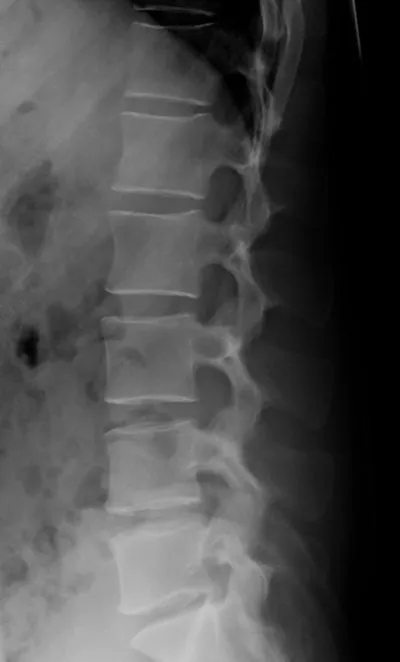

An X-ray showing more normal intervertebral spaces.

On the scan, the block-like things are the vertebral bodies and the triangular/trapezoidal shapes are the vertebral spines, those bumps that run down the middle of your own back. (These are bright white on the patient, more grayed out in the normal spine on the right.) You can see that the fourth vertebral body from the top (the second lumbar, or L-2) has slid backwards relative to the vertebral body below, which is called retrolisthesis. The space between the vertebral bodies in the middle of the image does not show the normal cushioning. The black areas are air bubbles between the vertebral bodies, caused by excessive stress pulling the vertebral bodies apart. There are also bony spurs sticking out from the tops and bottoms of the vertebral bodies in the middle of the image.